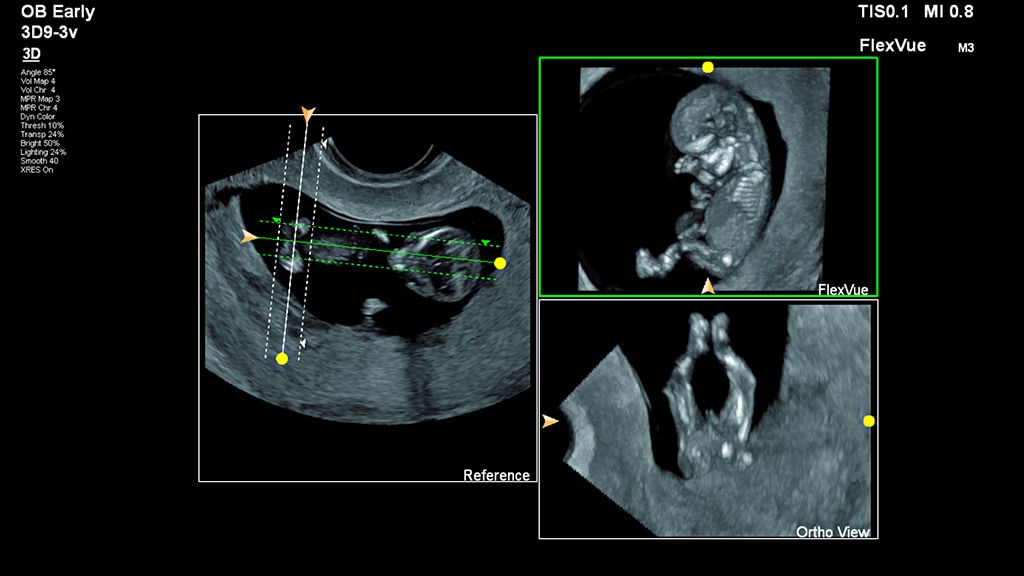

Demonstrated results using FlexVue

It (FlexVue) takes all of the complications out of MPR and manipulation of a surface-rendered volume. By deploying a straight line or a curved trace or continuous trace, we can take a curved image, flatten it out and make it a single planar image.